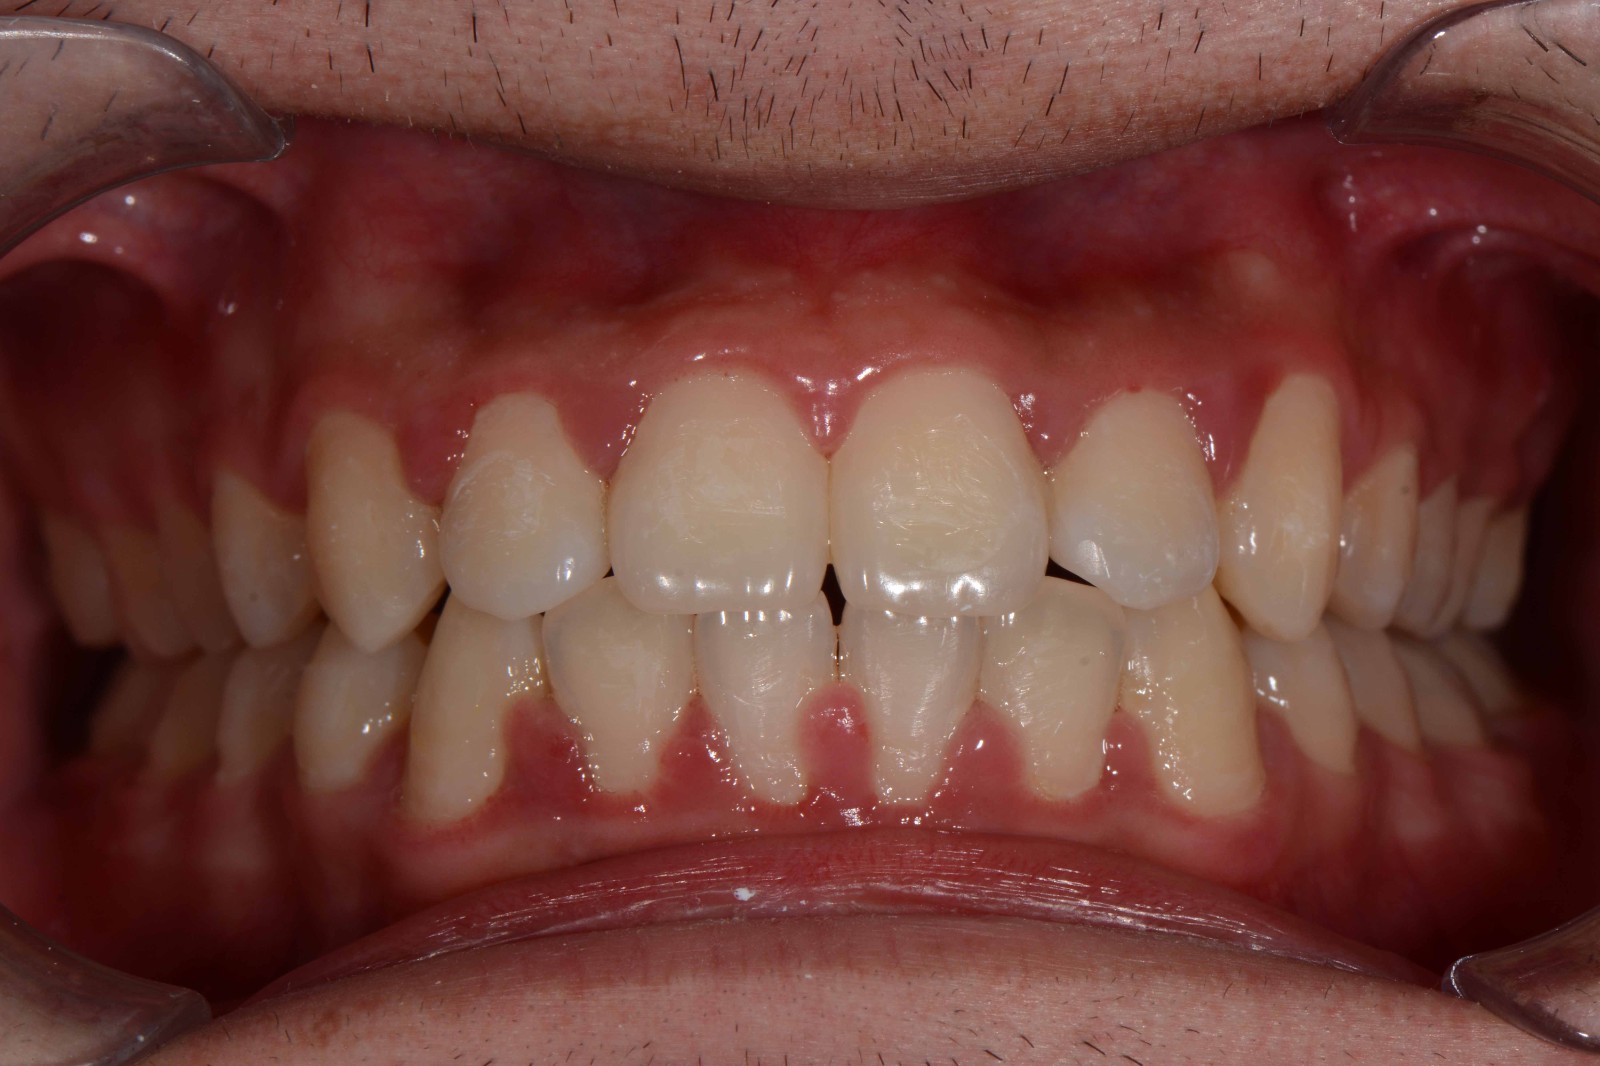

检查:拍摄口内面像照片,拍摄全景片侧位片,口扫,上下颌I-II度拥挤,中线不齐,局部反合,磨牙基本中性关系,上下前牙比较直立。

矫治前: